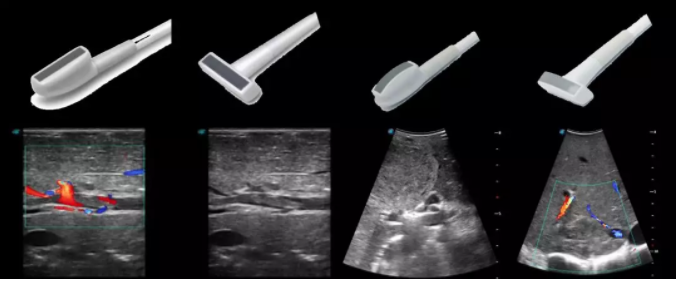

線陣/凸陣不同選擇,多種外形設(shè)計(jì)可以滿足適用于不同的臨床科室,滿足不同醫(yī)生的使用需求;

輕便小巧,方便持握;

防水、易消毒;

應(yīng)用科室:手術(shù)室、肝膽外科、消化外科、腫瘤科、心胸外科、泌尿外科、婦產(chǎn)科等

實(shí)時(shí)觀察穿刺針進(jìn)入血管的全過程,方便操作及較短的穿刺路徑,智能進(jìn)針尺寸提示,讓置管工作更加輕松,高效。

不同進(jìn)針路徑